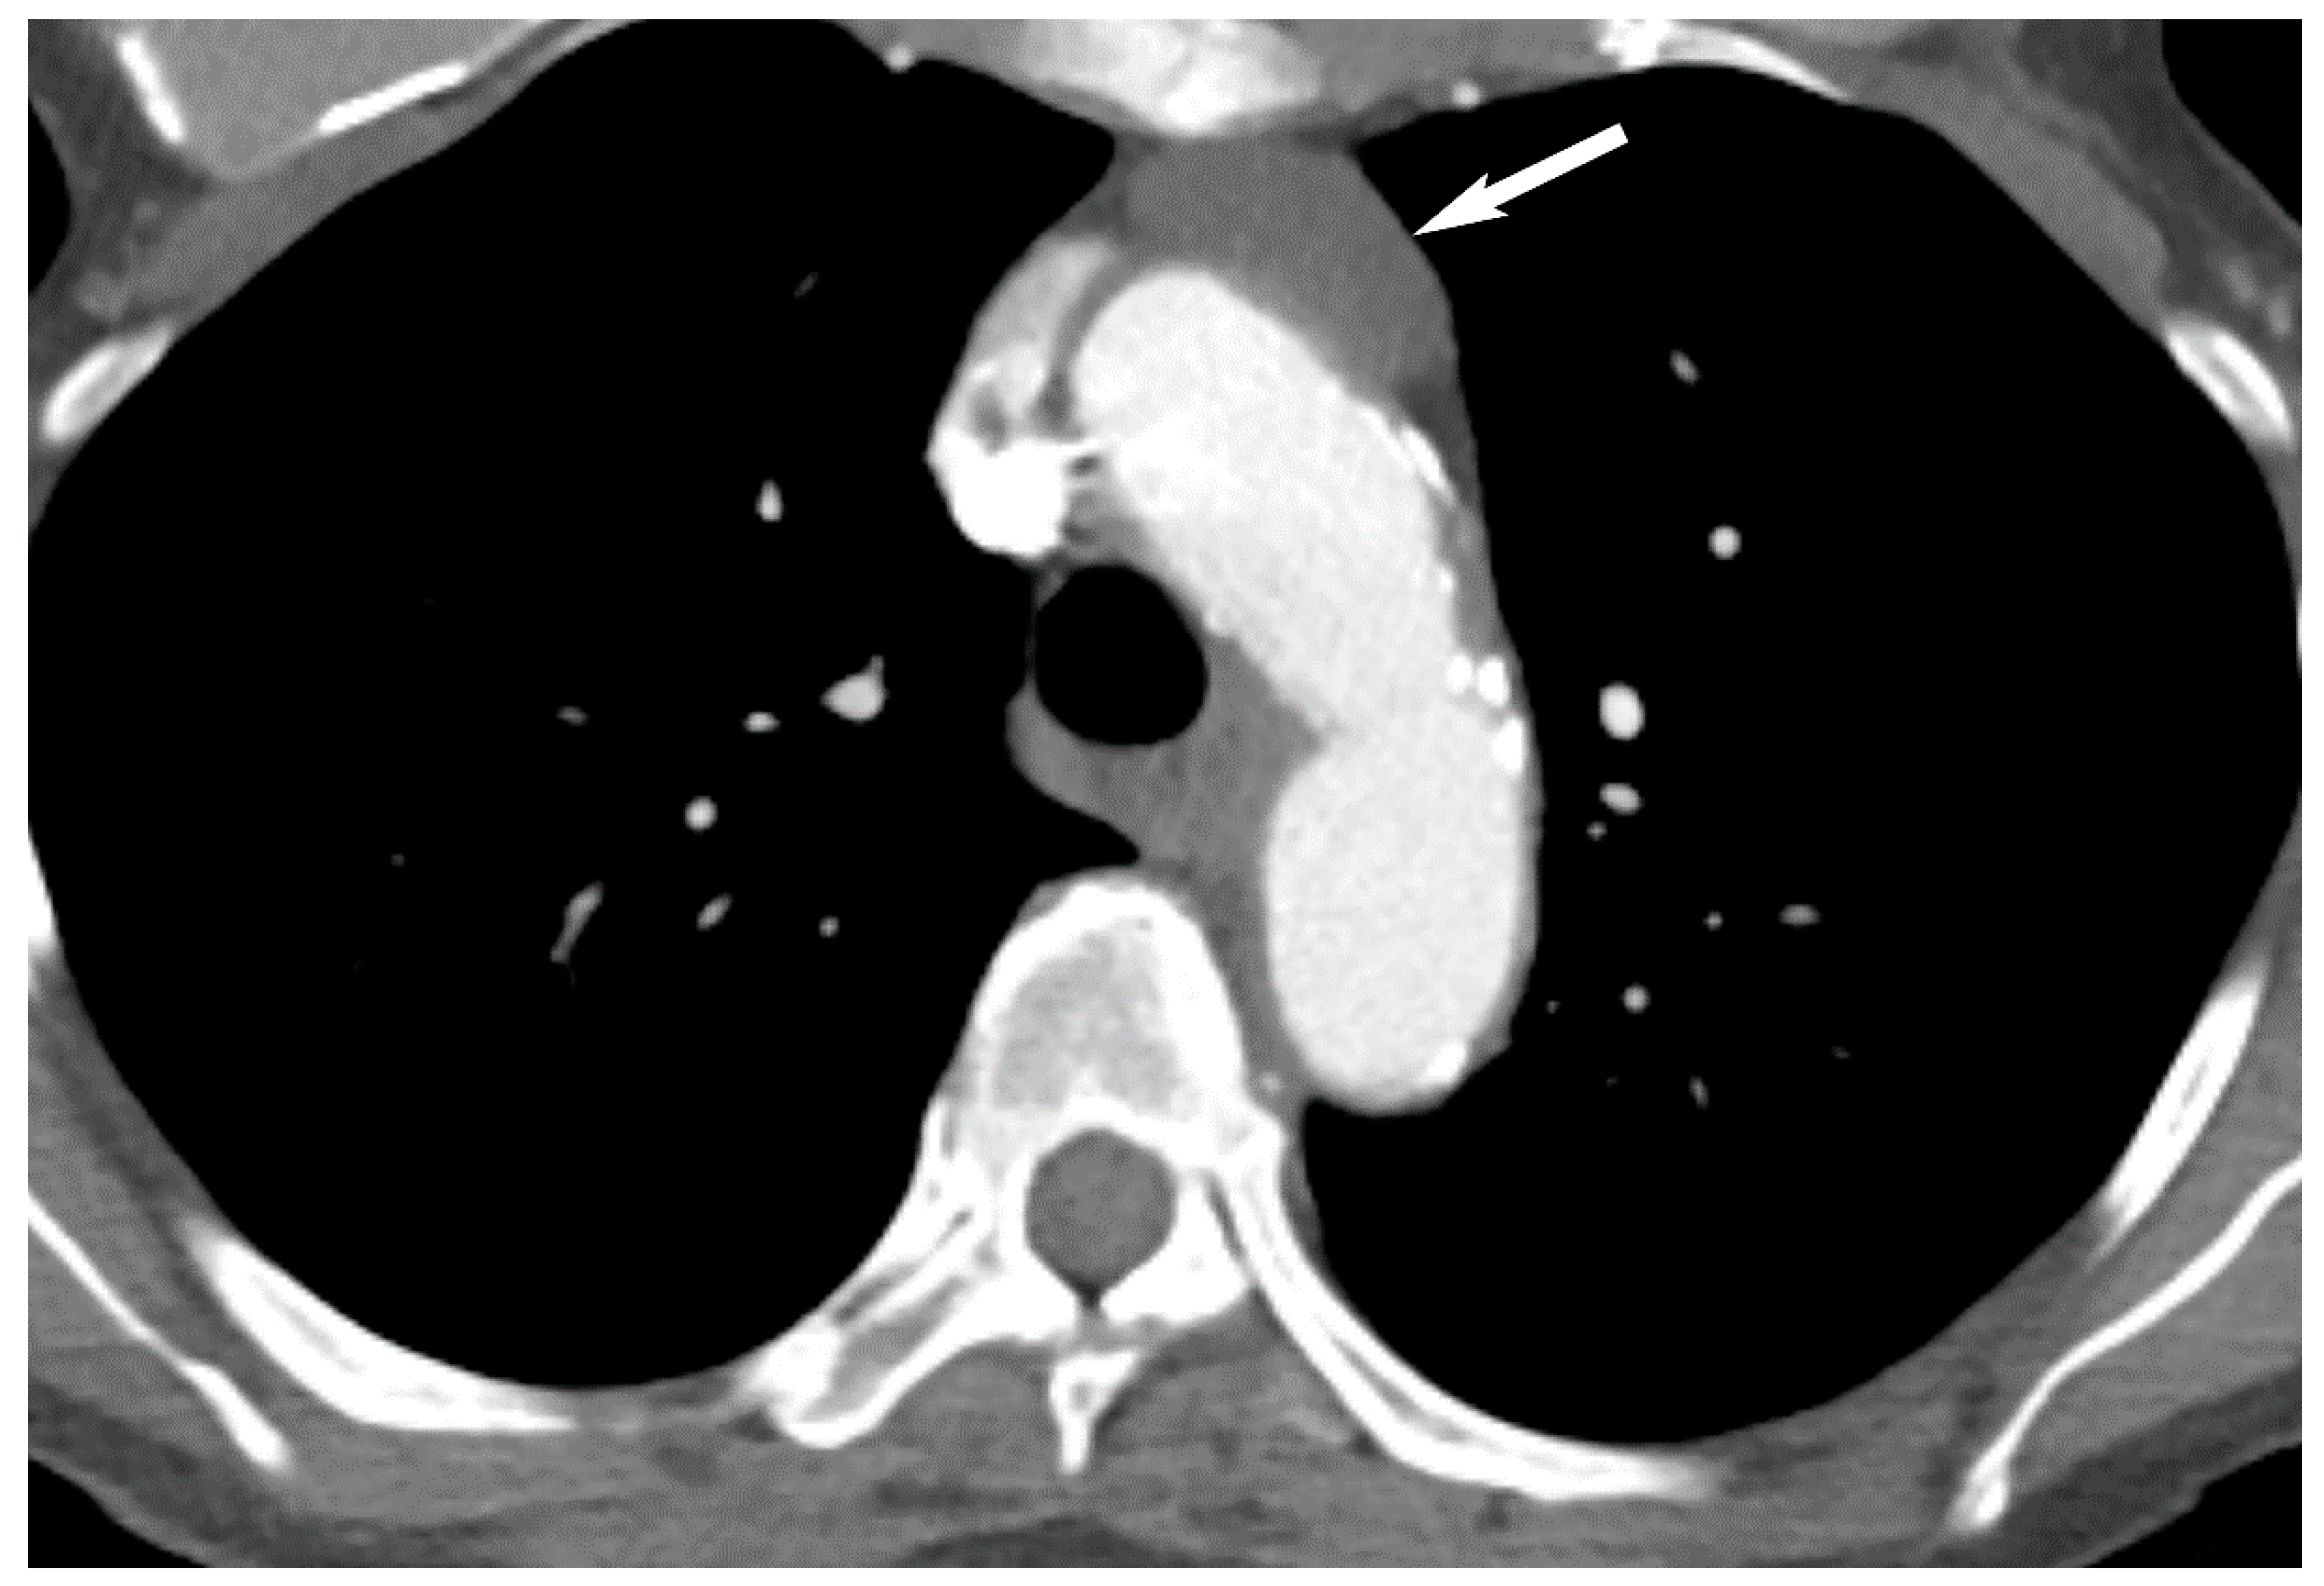

9. Hypervascular Lesions

7. Germ Cell Tumors